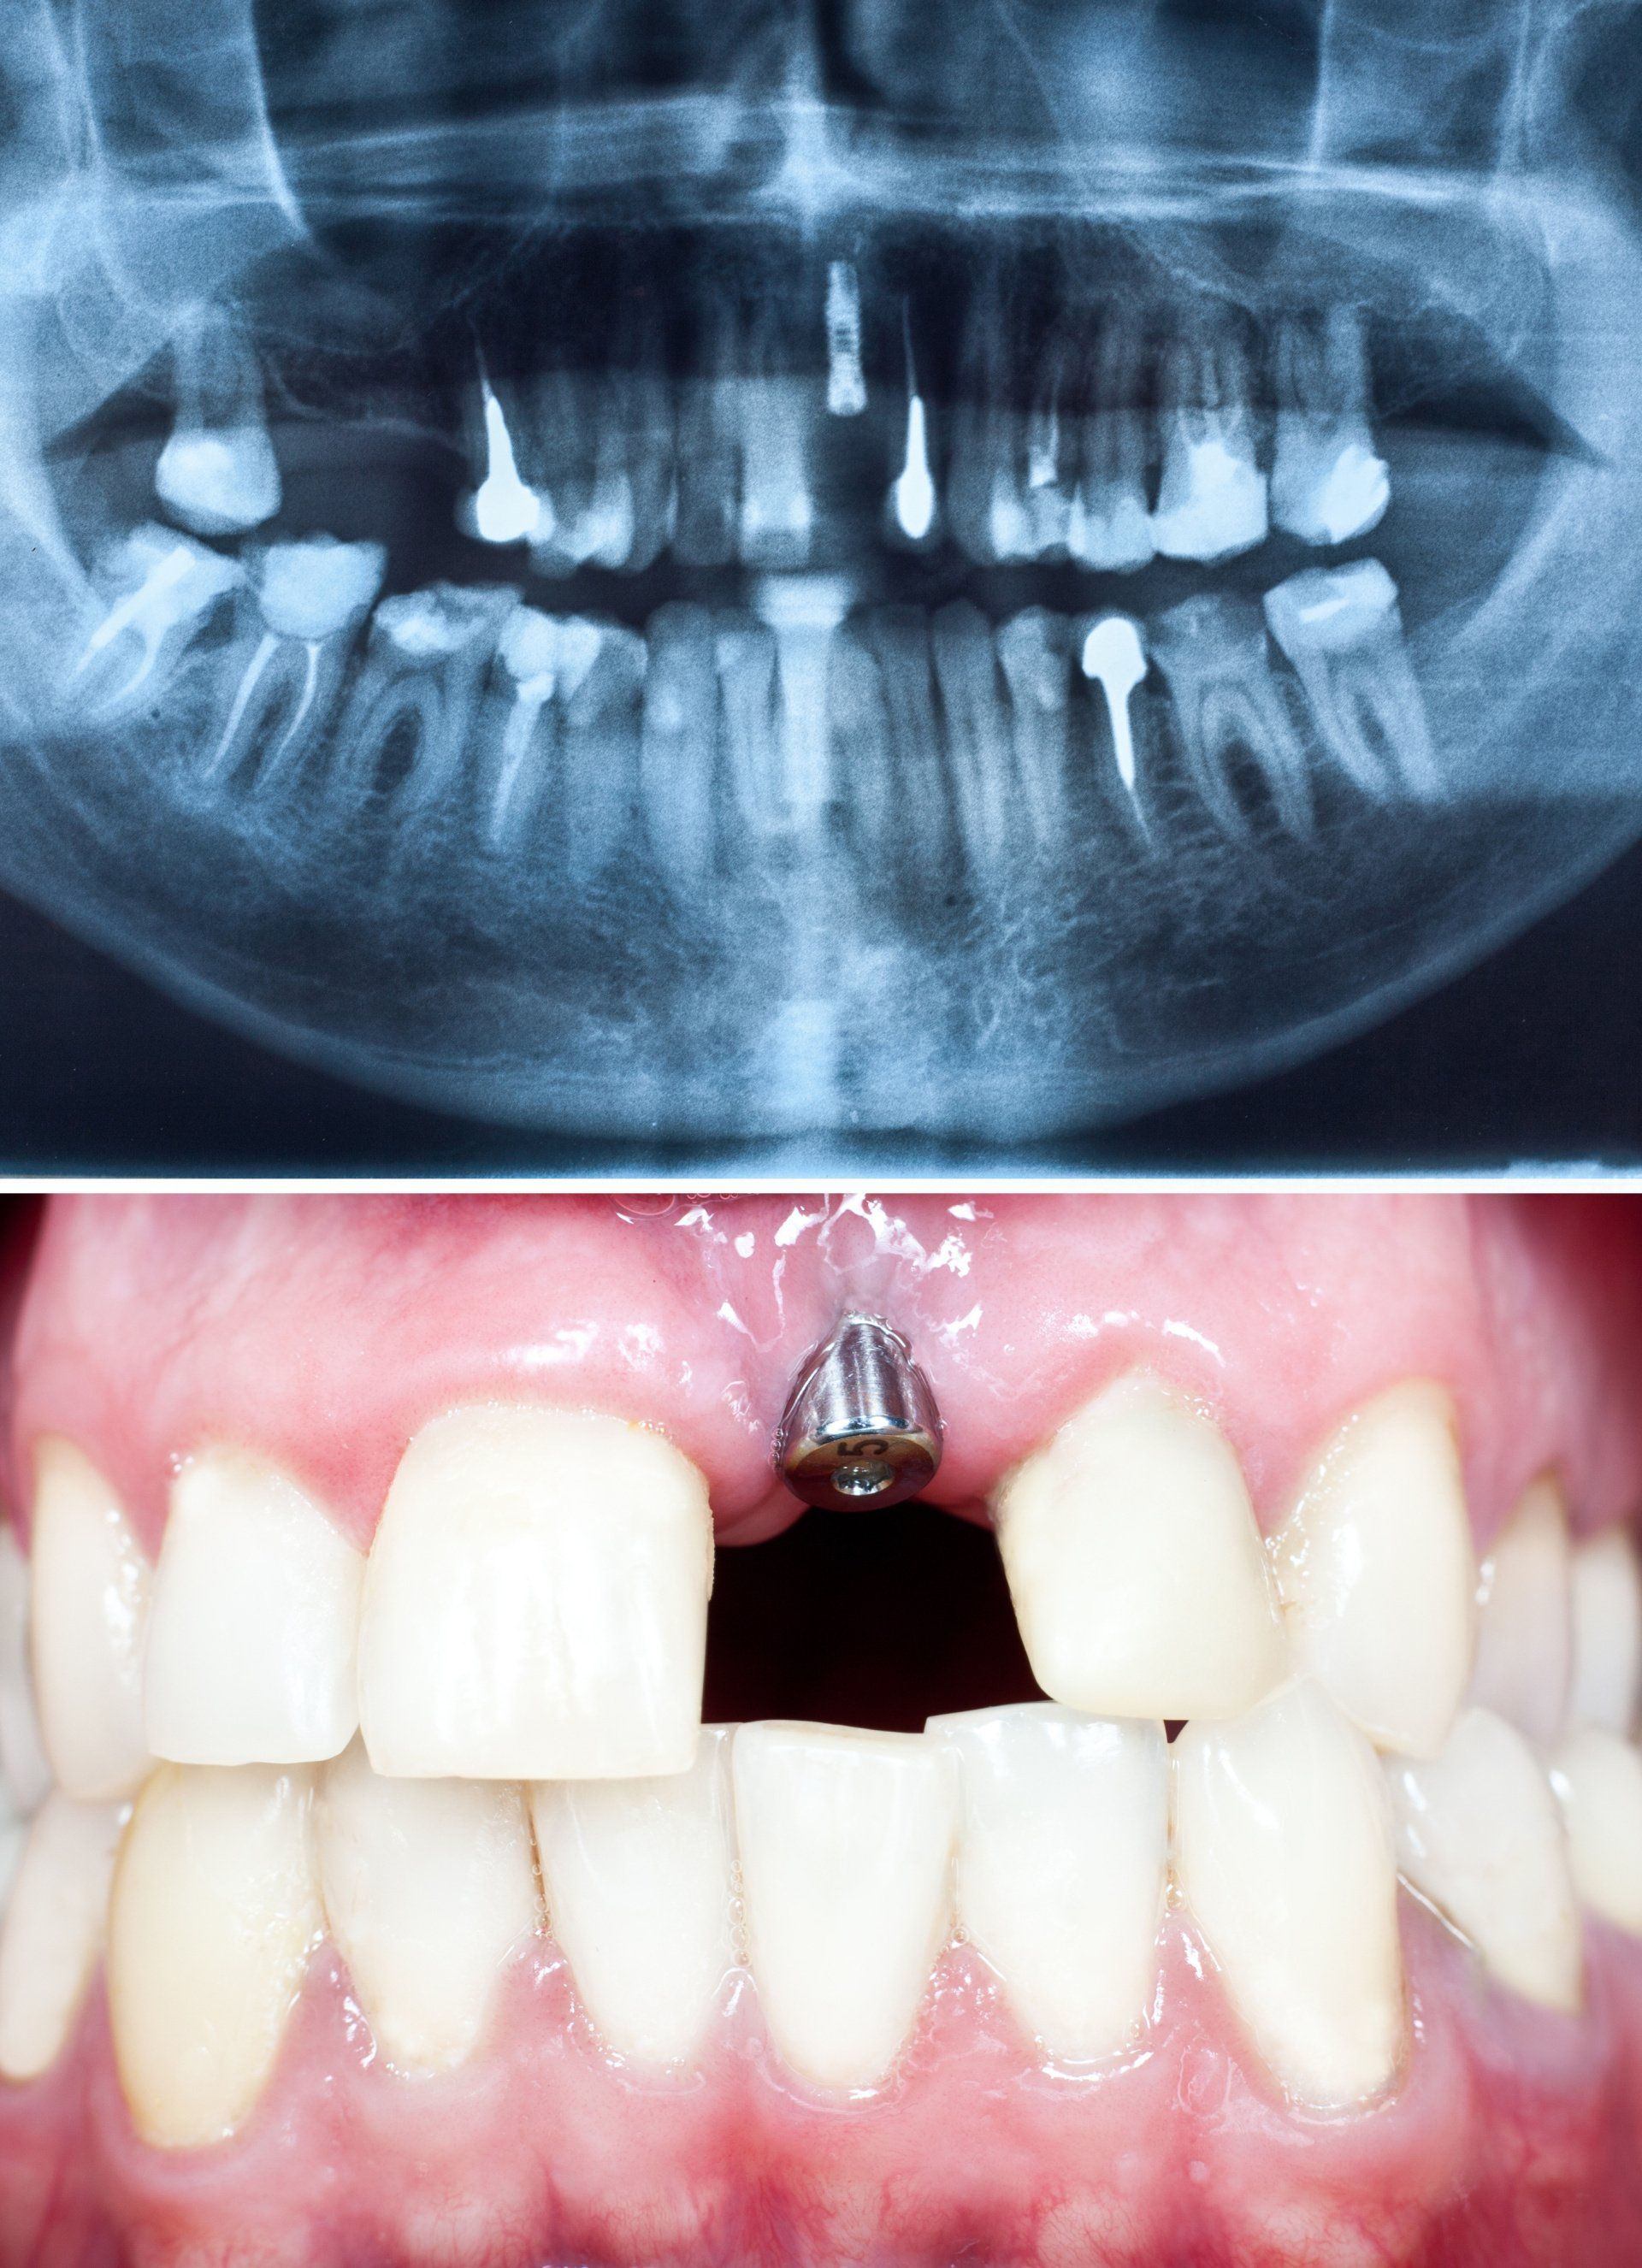

L’implantologia a carico immediato è una procedura con cui si fissa la protesi agli impianti dentale, viti in titanio puro o in lega di titanio e zirconio. L'impianto si avvita nell’osso, sotto la gengiva, e sostituisce a tutti gli effetti la radice dei denti naturali mancanti.

Agli impianti vengono, quindi, ancorati i nuovi denti fissi.